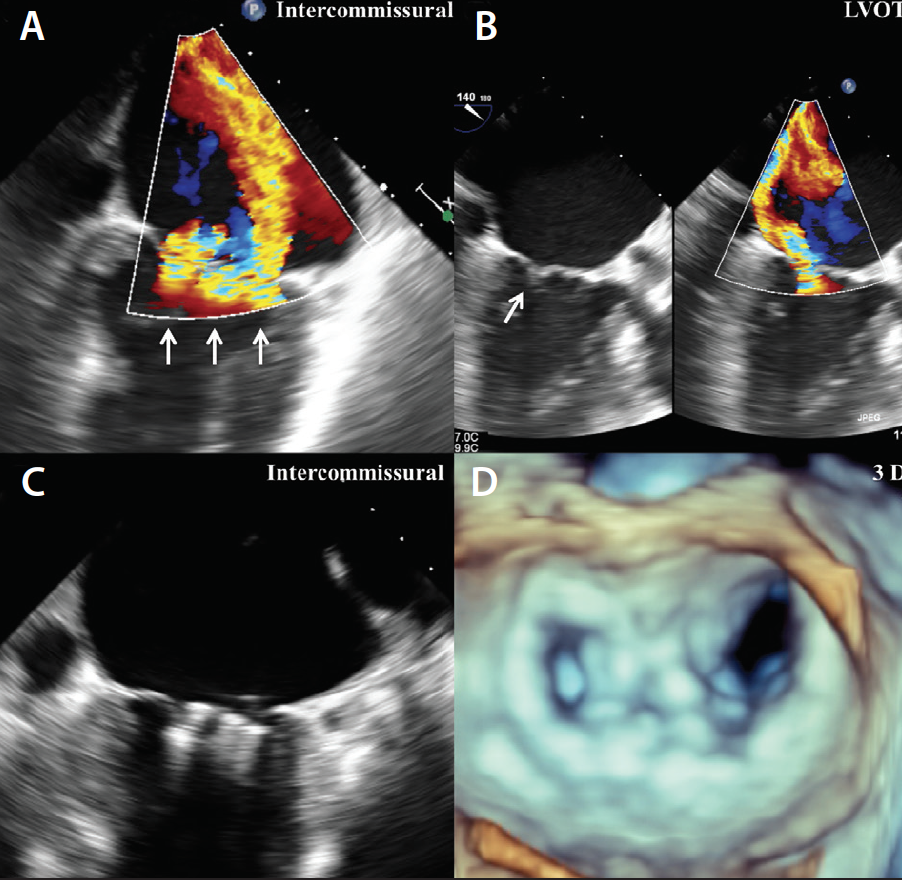

Figure 2. Example of functional MR; ischemic cardiomyopathy on the posterior wall resulted in severe MR due to restricted posterior leaflet. Intercommissural view showing wide regurgitant jet (A). LVOT view showing restricted posterior leaflet with posterior directed jet view (B). Intercommissural view showing three clips placed in A2-P2 mitral valve leaflet (C). Three-dimensional view showing a double orifice created by three MitraClips (D).